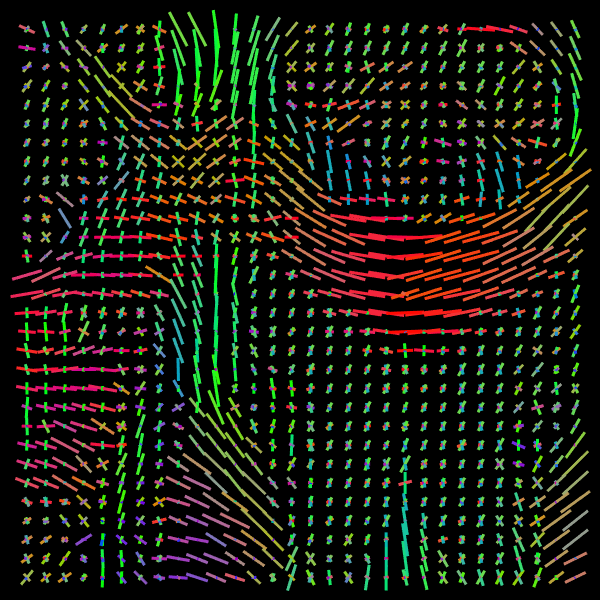

We use the Diffusion Multi-Tensor Model implementation in the DiPy library (Garyfallidis et al., 2014) to generate the signals. Figure 1 shows the Orientation Distribution Function (ODF) of a generated patch. One can appreciate smooth variations of the tensors orientation.

Figure 1: Neighborhood representation